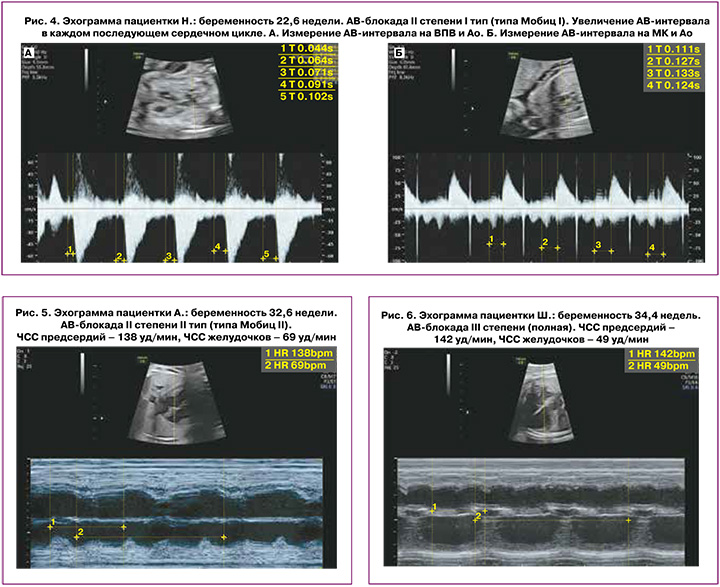

При I типе (Мобитц типа I) характерно постепенное замедление АВ-проводимости от цикла к циклу, которое заканчивается полным перерывом проводимости (выпадение желудочкового сокращения). Затем проводимость восстанавливается, и описанный комплекс повторяется снова. Такой периодический процесс называется периодикой Самойлова–Венкебаха (рис. 4, а и б).

АВ-блокада II степени типа Мобитц II характеризуется внезапной (без предварительного удлинения времени проведения по АВ-узлу) блокадой изолированного импульса. Временной интервал между последовательными предсердными сокращениями при этом типе АВ-блокады одинаковый, но распространение электрического импульса к желудочкам прерывается, каждое второе (третье) сокращение предсердий не проводится на желудочки, частота сокращений желудочков в кратное число раз меньше, чем частота сокращений предсердий (например, 2:1, 3:1) [35] (рис. 5).

Полная АВ-блокада (III степени) возникает при полном прекращении передачи импульсов возбуждения из предсердий в желудочки сердца. Предсердия сокращаются в своем ритме под влиянием импульсов из синусового узла, желудочки сокращаются в более редком ритме под действием импульсов из автоматических центров второго или третьего порядка (АВ- диссоциация). При этом частота сокращений желудочков составляет 50–80 уд/мин, но может быть ниже (рис. 6). При такой частоте сокращений желудочков могут развиваться сердечная дисфункция и водянка плода. Полный АВ-блок встречается с частотой 1:15000–22000 новорожденных [35].